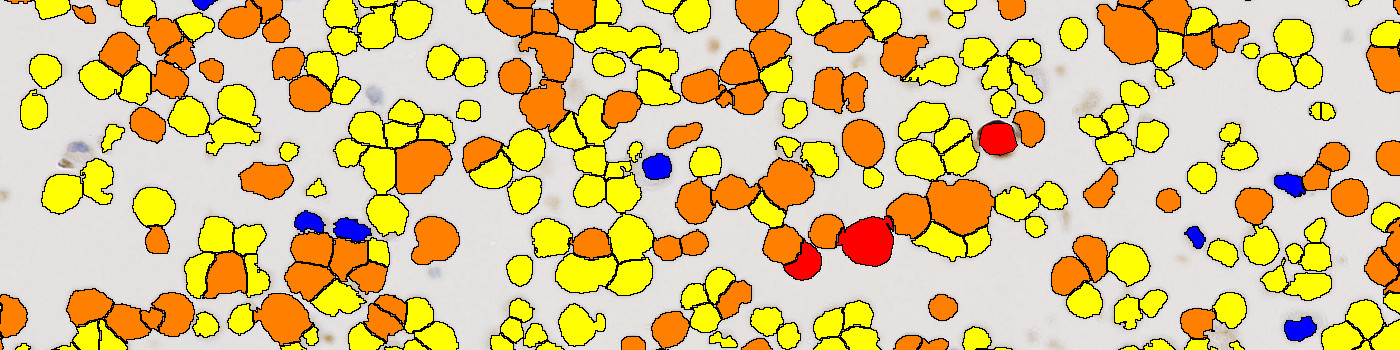

The ROS1 analysis algorithms for ONCOtopix®, supports the analyser in obtaining accurate, precise quantification of biomarker expression for ROS1 protein. The APP can be configured to provide positive ratio or H-Score. Based on the H-score output, it is possible to Identify the negative, intermediate and positively reacting cores.

The combination of IHC HDx™ Cell lines and the ONCOtopix with the ROS1 APP, provides is the basis of a high quality regent QC system.